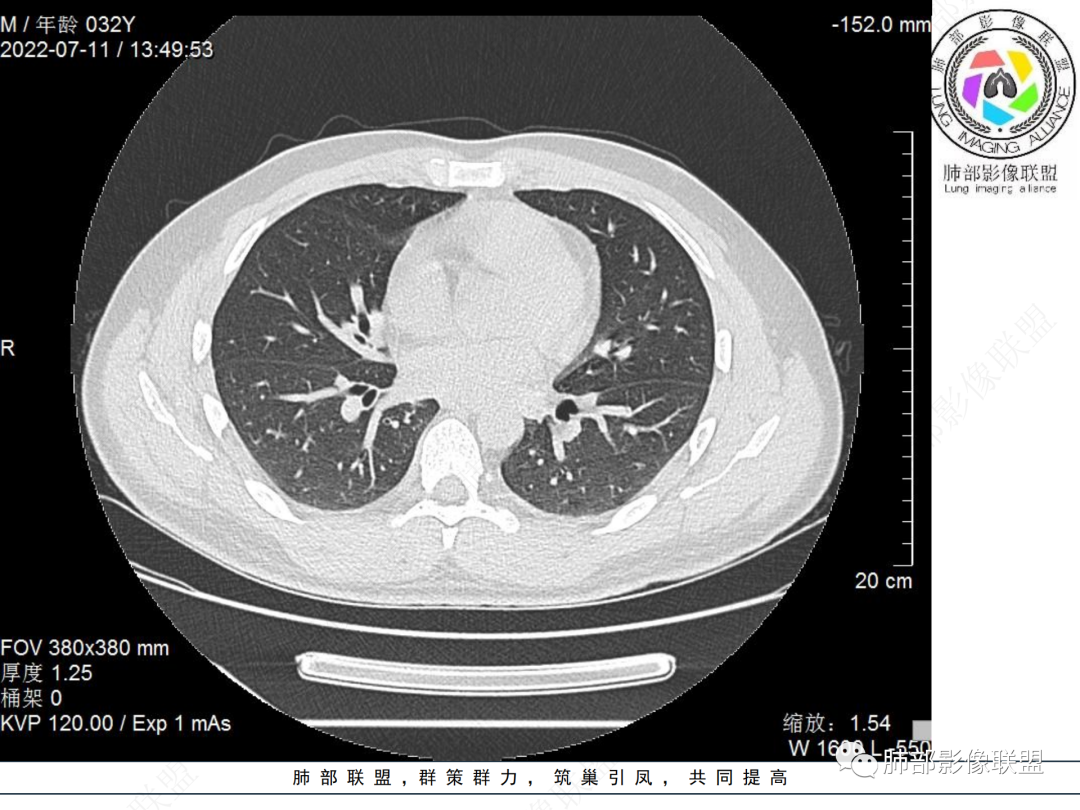

左肺下叶后基底段开口处结节,边缘光滑清楚,没有增强扫描,年轻男性患者痰血三天,考虑1.良性病变:腺瘤、错构瘤、平滑肌瘤

2.恶性:类癌、粘液表皮样癌。

左肺下叶外后基底段气管内见结节状影,边缘部分清晰。考虑错构瘤,待排恶性病变。

左肺下叶气管内外占位病变,咯血病史,考虑类癌,粘表待排。

青年男性,左肺下叶后基底段支气管开口软组织结节,边缘光整,气管镜提示质软,易出血,考虑类癌

左肺下叶气道腔内占位,远端无花花草草,疾病谱:鳞,类癌,粘表,腺样囊腺癌,小,无增强,不好判断,临床咯血,选类癌。

左肺下叶后基底段开口处结节影,边缘光滑,患者年龄较小,首选类癌

左肺下叶后基底段开口处腔内见壁结节,花生米样,宽基底,补充增强及矢状位重建,确定我无向壁外突破浸润生长,另见强化的特点,临床触之易出血,类Ca可能性大。

年轻男性,咳血,左肺下叶后基底段支气管腔内结节,边缘光滑,首先考虑青年三件套,类癌大于粘液表皮样癌,支气管镜质软,触之易出血,鉴别血管瘤,平滑肌瘤

左肺下叶后基底段开口部结节,密度较均匀一致,边缘较光整,目测密度偏低,支气管镜示:质软、触之易出血,考虑恶性,类癌。

左肺下叶后基底段支气管腔内结节,有蒂,容易出血,先考虑良性病变,肉芽组织型血管瘤,与类癌鉴别。

IMT常表现为边缘清晰的周围型结节或肿块,一般体积相对较大。大约10%-20%发生于支气管及气管腔内,表现为中央型病变,一般为单发。IMT胸部CT显示90%为单发结节或肿块。